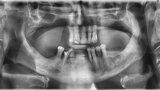

Osteonekroza występująca po zastosowaniu bisfosfonianów